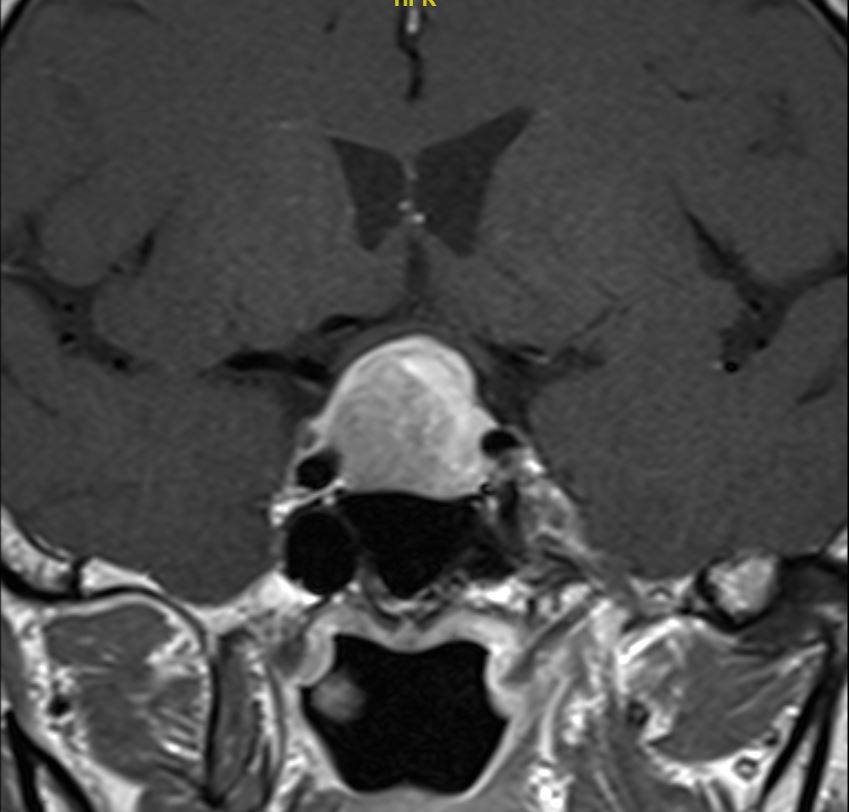

患者为63岁患者,因头痛伴有视物模糊2个月前来就诊,检查头颅MRI检查发现鞍区占位性病变,肿瘤大小2.3cm,向上生长压迫视交叉,两侧侵犯海绵窦。

增强冠状位